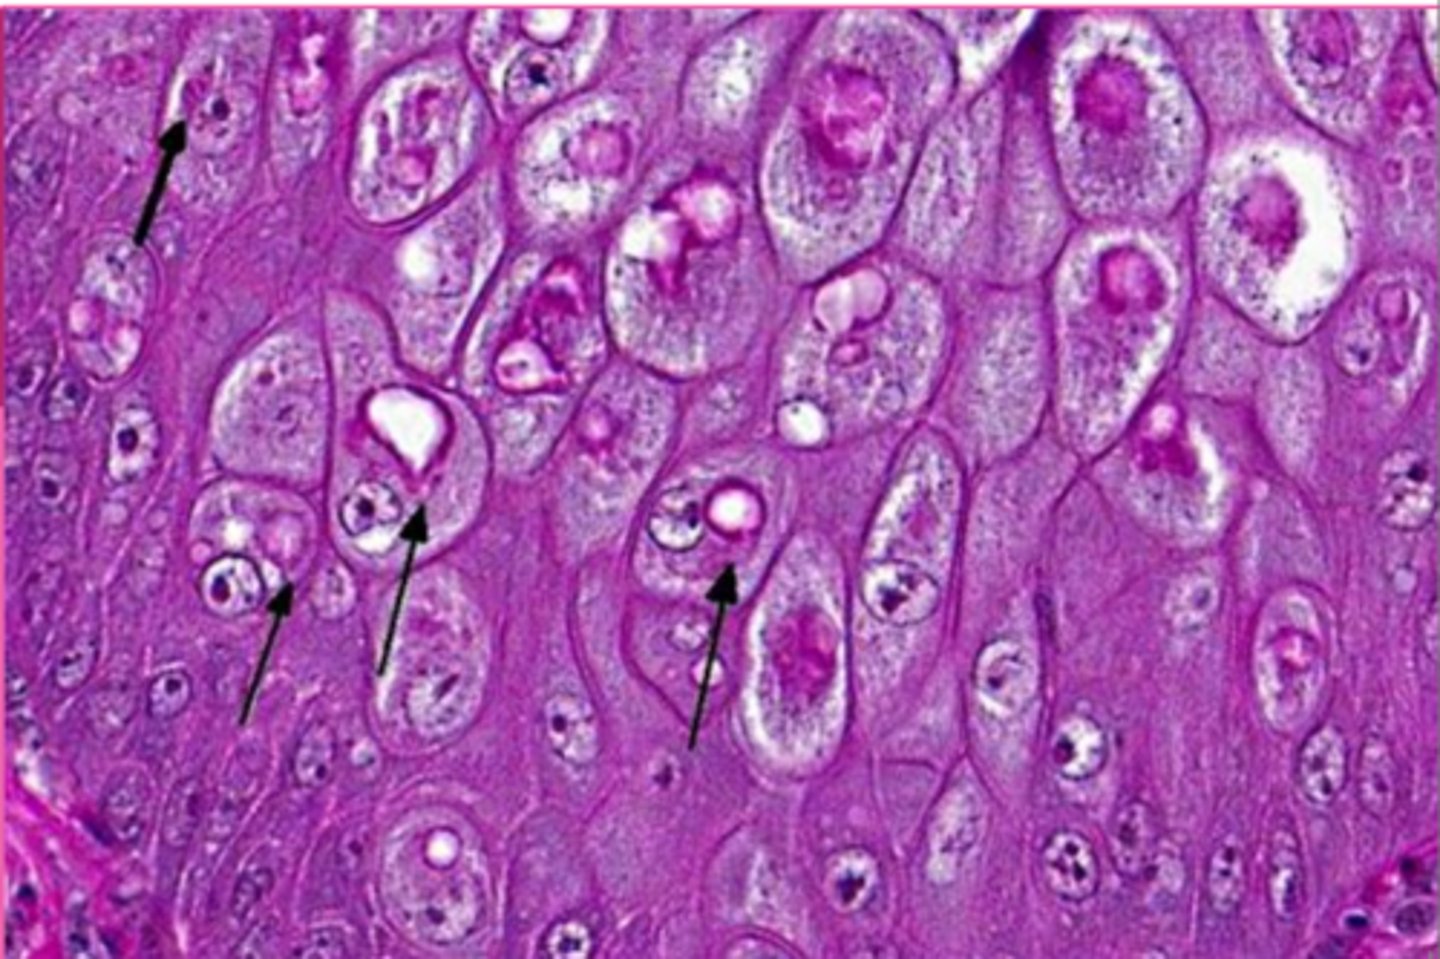

displaced nucleus

blue arrow

<p>blue arrow</p>

macrocytic lipidosis - large cytoplasmic vacuole

yellow circle?

<p>yellow circle?</p>